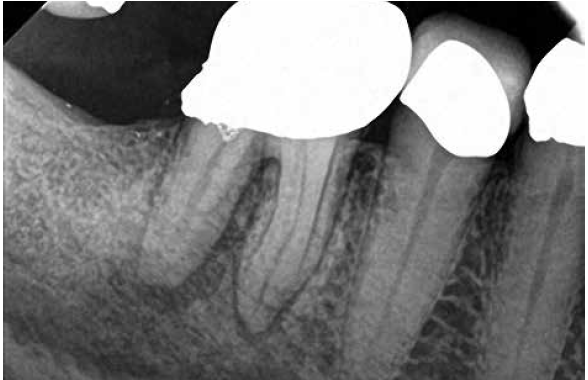

A body of research has emerged in recent years on the management of severe dental pain, exemplified by the diagnosis of an acute apical abscess where drainage cannot be achieved, symptomatic apical periodontitis, or irreversible pulpitis.11 An example of an acute apical abscess is depicted in Figure 1 and Figure 2. These conditions typically represent the most severe discomfort experienced by patients, and consequently, they serve as an excellent model for pain management. Treatment strategies for these issues and other painful conditions should include both definitive treatments for the diagnosed condition as well as adjunctive pharmacologic management.

(1.) A 74-year-old male presented with an acute apical abscess associated with tooth No. 30. The pre-operative periapical x-ray revealed evidence of apical pathology.

Figure 1